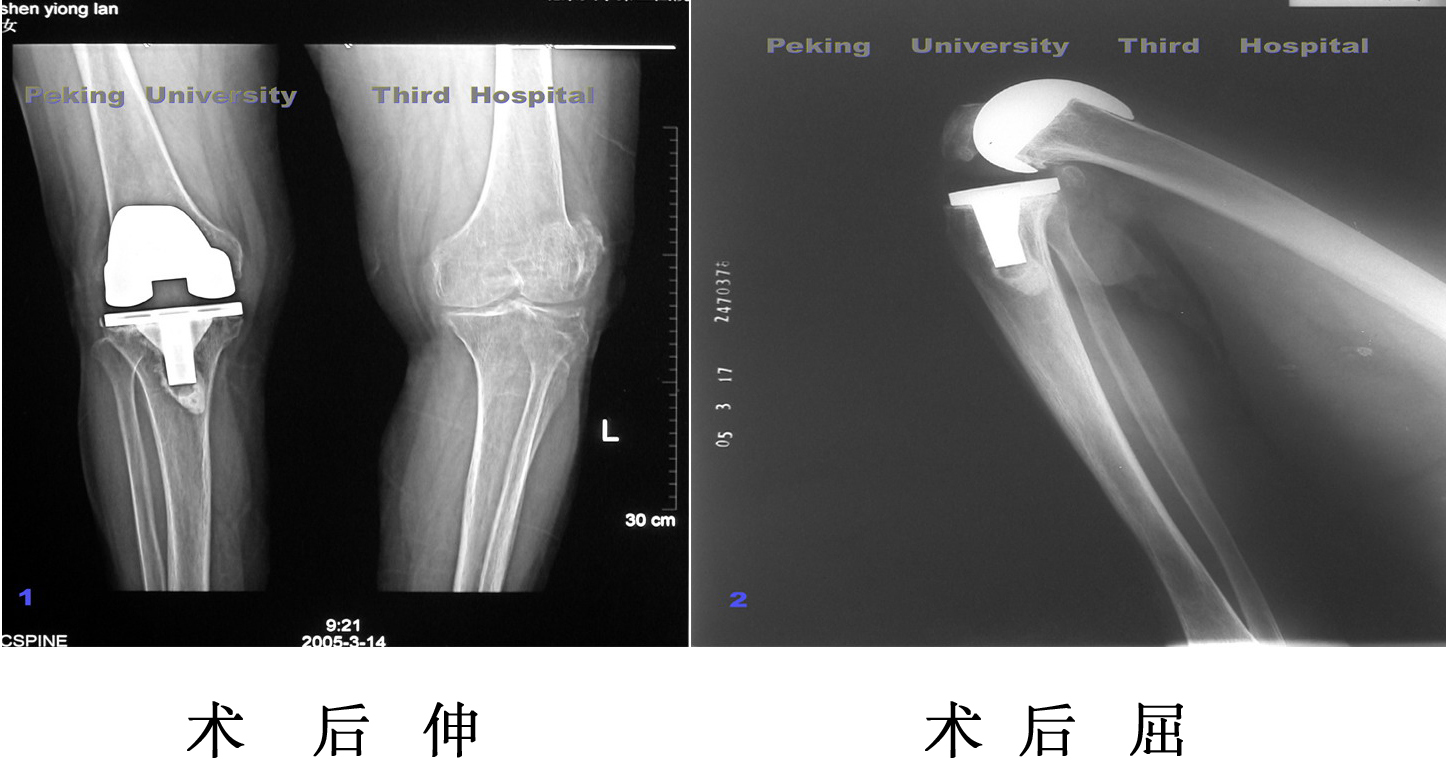

10年前因为膝关节骨性关节炎在我院接受关节置换手术,手术后疼

痛消失功能改善。2001年摔伤导致膝关节周围骨折,再次接受关节置换

手术,患者在病房过了90岁生日。现在关节功能良好,可以自己走路。

膝关节功能

PFC假体手术后1年到达145度高膝度。国外此种假体通常可

以到达120度屈膝。普通假体达到了高屈。